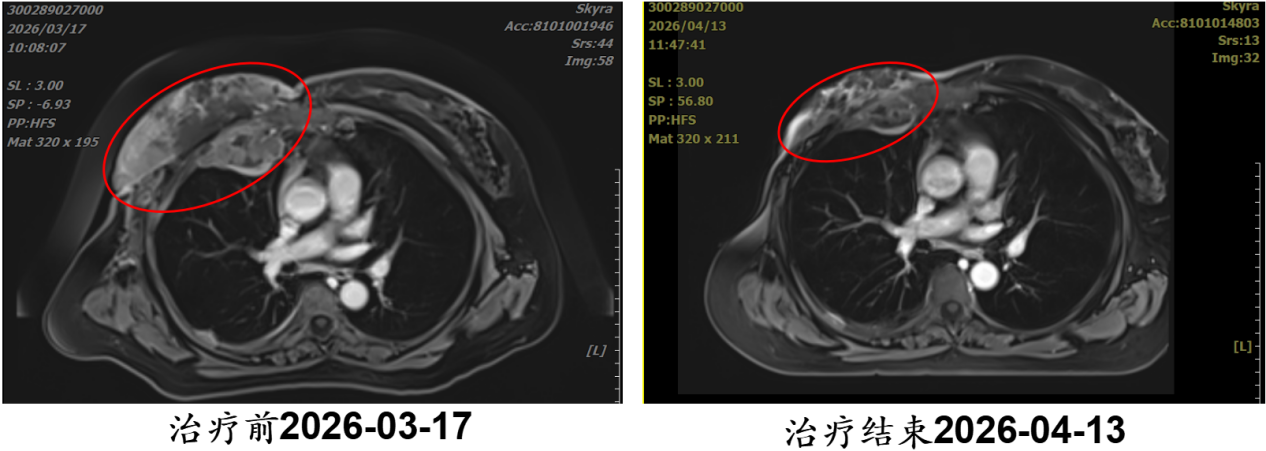

病例6:赵某某,男,61岁

· 诊断:左肺下叶恶性肿瘤颈部淋巴结转移侵及皮肤并破溃,鳞状细胞癌,cT3N3M1 Ⅳ期

· 难治点:肿瘤侵及皮肤并破溃,局部晚期,常规治疗手段有限

· 重(碳)离子治疗:疗程3周

· 结果:治疗结束时,肿瘤明显缩小,破溃处缩小接近愈合

点评:重(碳)离子为晚期破溃性肿瘤提供了理想治疗手段。

【病例提供医生:张雁山 科室:放疗中心一科】